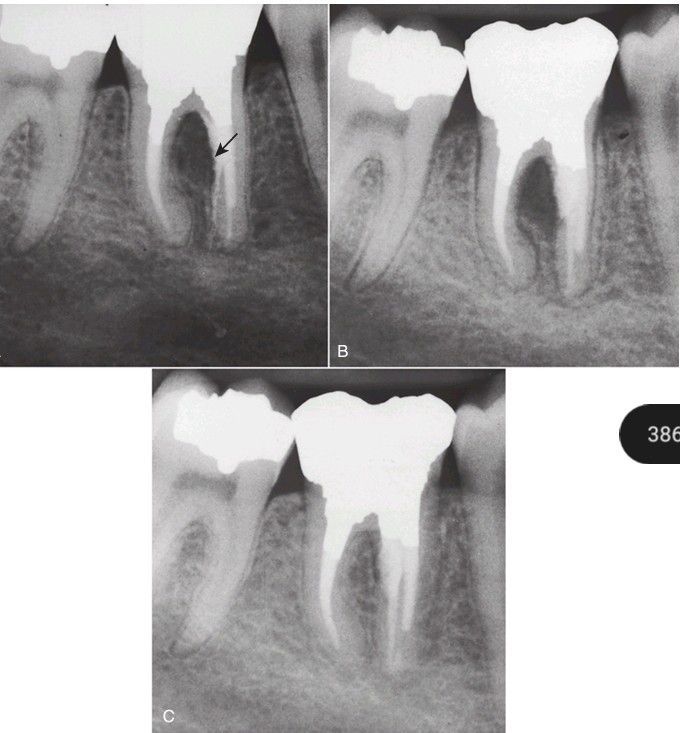

(A) Furcation perforation results in extrusion of material (arrow) and pathosis. (B) After flap reflection and exposure, the defect is repaired with mineral trioxide aggregate. (C) Evaluation at 2 years shows successful healing